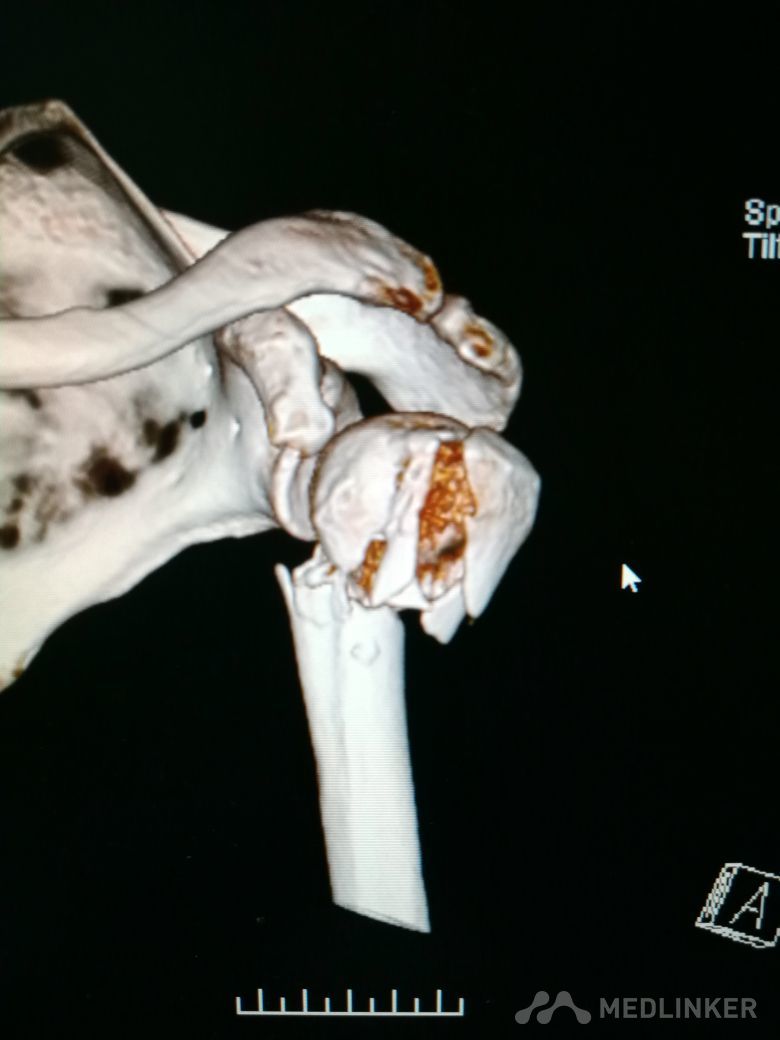

肱骨近端骨折 Neer IV型

患者,女性,55岁,因外伤致左肩疼痛六小时入院,既往无其他慢性病史

查体 右肩肿胀,畸形,活动受限,压痛,皮下淤血,右桡动脉搏动存在

完善相关检查,在腰麻下行右肱骨近端骨折切开复位内固定术

肱骨近端骨折占到肱骨骨折的45%,肱骨近端锁定钢板具有低切迹、高弹性、生物力学性能优良等特点,可以起到角度稳定控制旋转的作用。但是对于严重粉碎性肱骨近端骨折而言,单纯的肱骨近端锁定钢板不一定能够提供稳定的固定,手术之后仍有可能出现内翻塌陷、前后成角、螺钉切出、骨折畸形愈合、骨折不愈合等并发症。